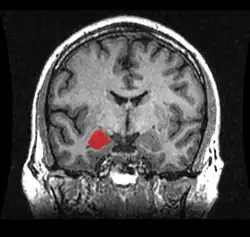

Миндалевидное тело (лат. corpus amygdaloideum), ами́гдала[1] — область мозга миндалевидной формы, находящаяся в белом веществе височной доли полушария под скорлупой, примерно на 1,5—2,0 см сзади от височного полюса. В мозге два миндалевидных тела — по одному в каждом полушарии[2]. Миндалевидное тело играет ключевую роль в формировании эмоций, в частности, страха. У пациента, миндалевидное тело которого оказалось полностью разрушено вследствие болезни Урбаха — Вите, наблюдалось отсутствие страха[3][4][5]. Миндалевидное тело также играет важную роль в функционировании памяти, принятии решений и эмоциональных реакциях[6]. Миндалевидное тело является частью лимбической системы, относится к подкорковым обонятельным центрам.